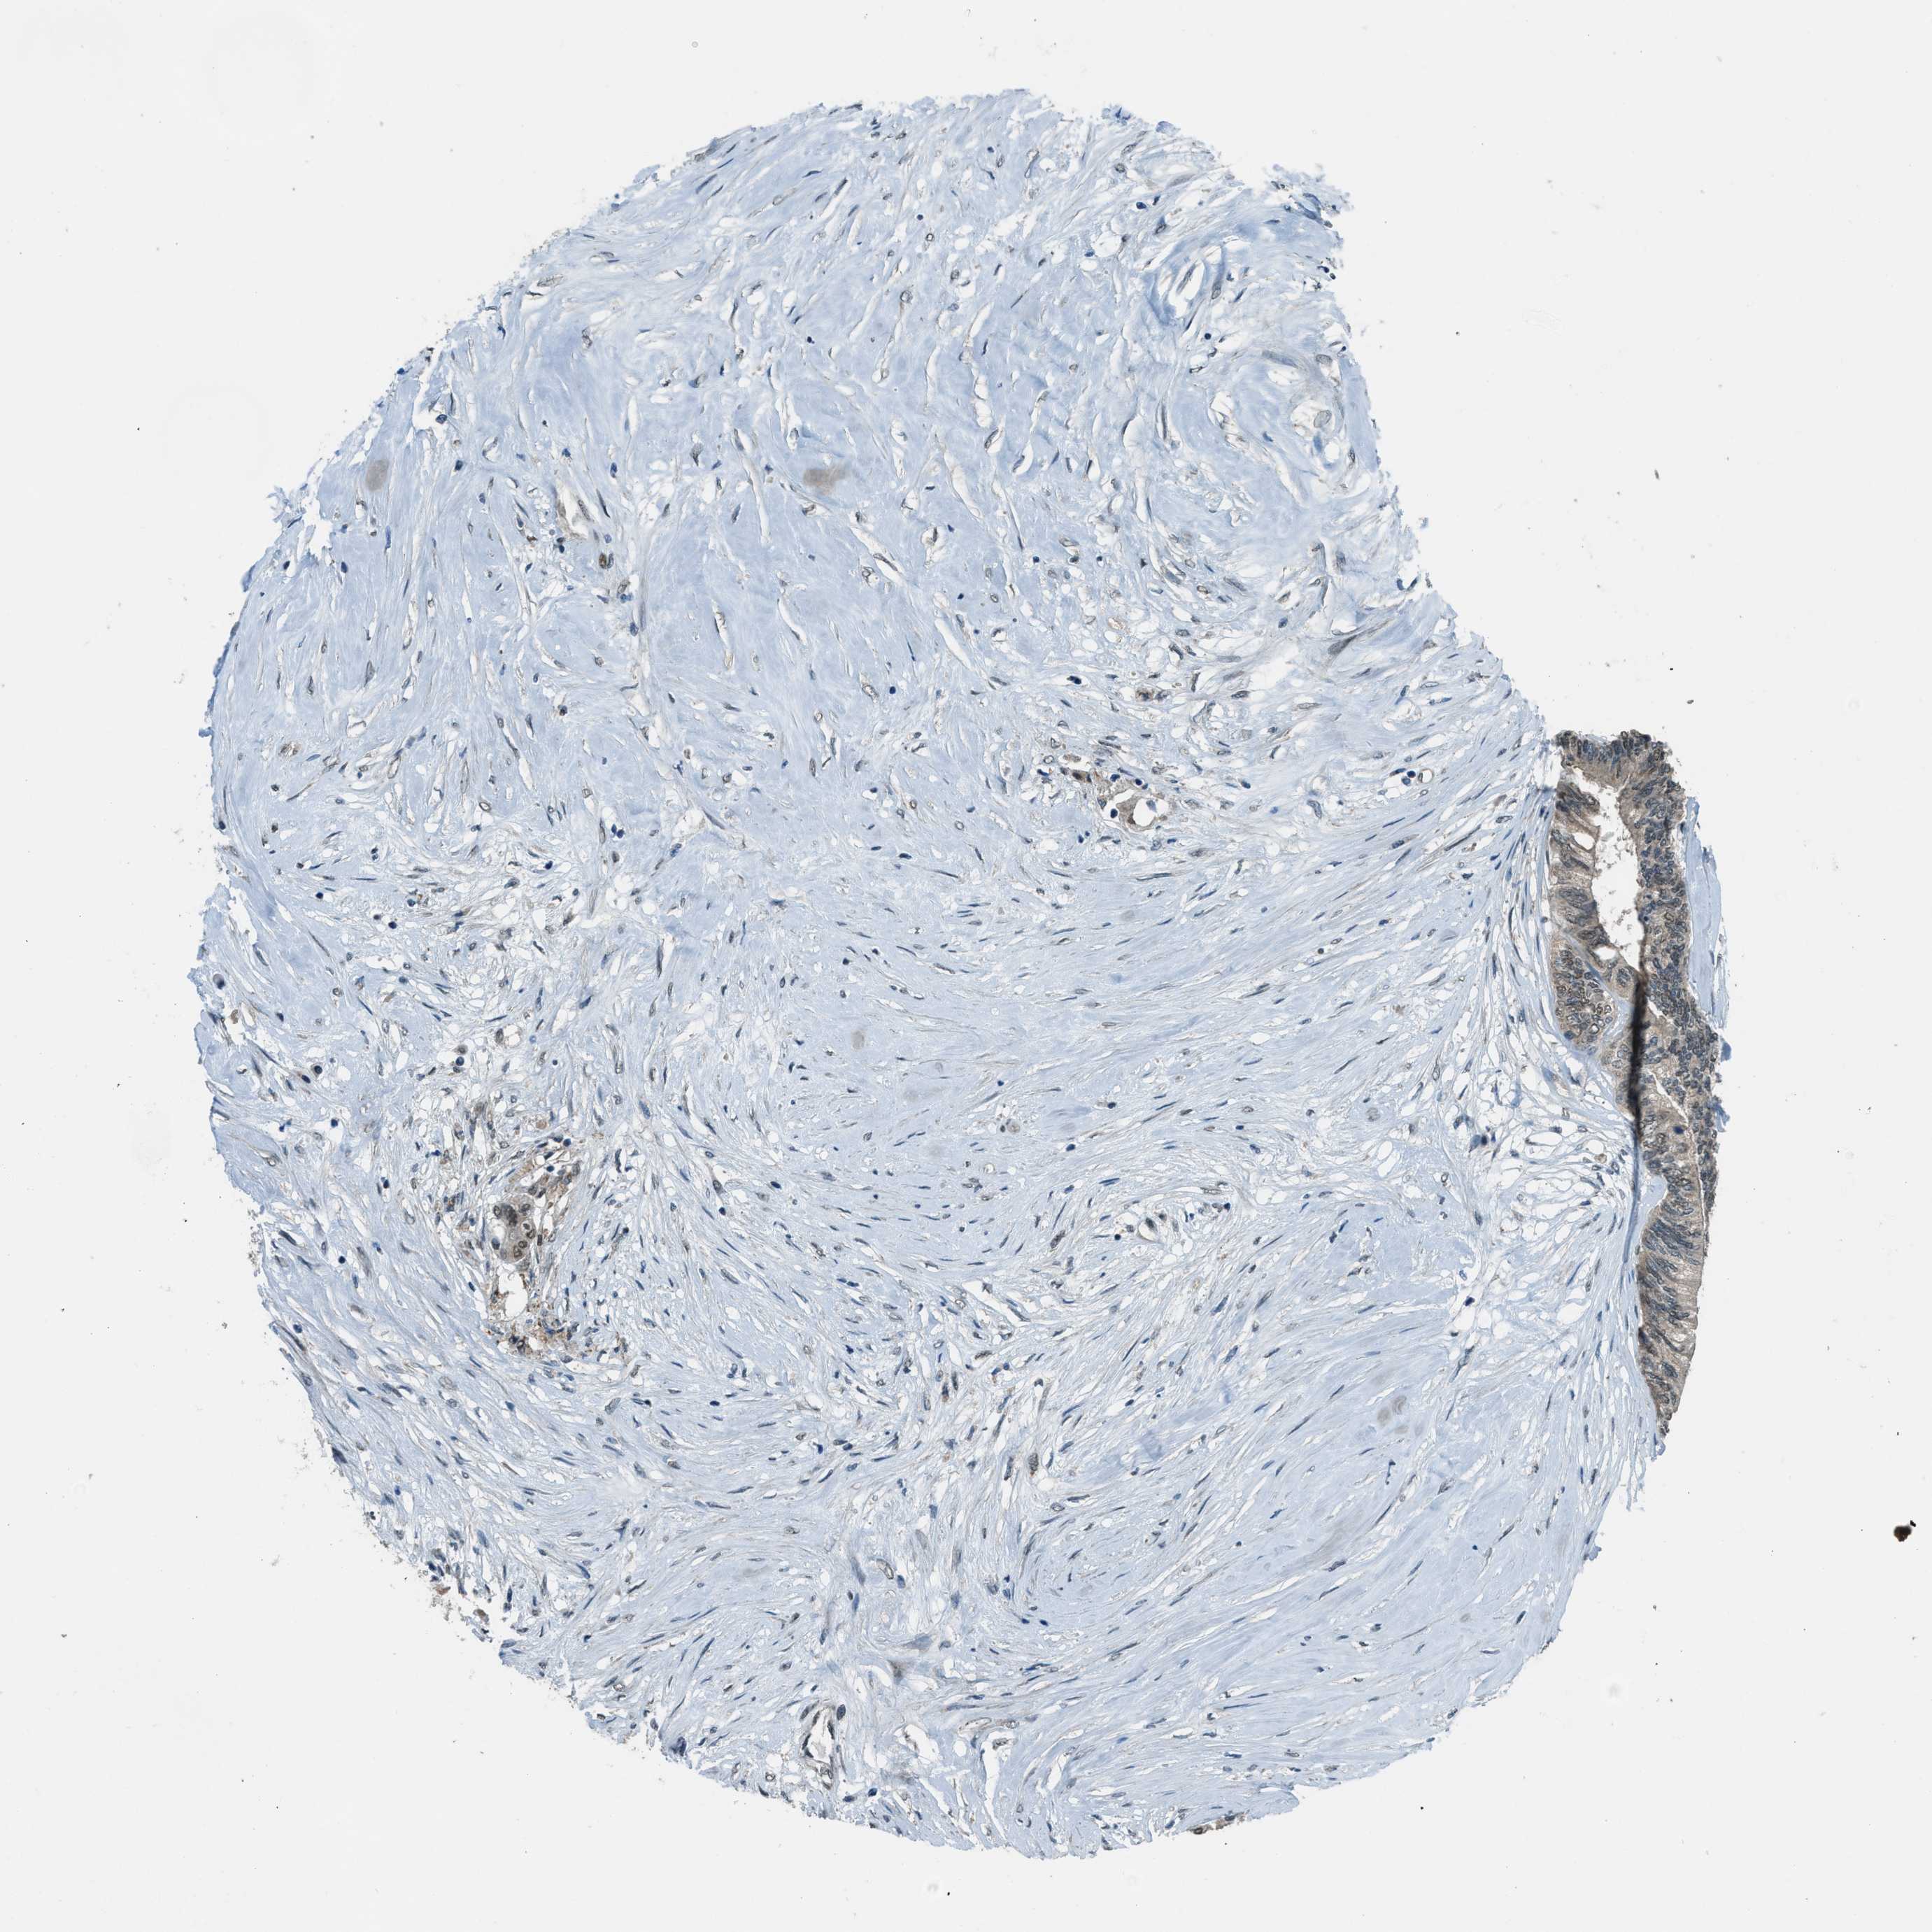

CANCER COLORECTAL CANCER Show tissue menu

Colorectal cancer

Human cancer

Colon adenocarcinoma